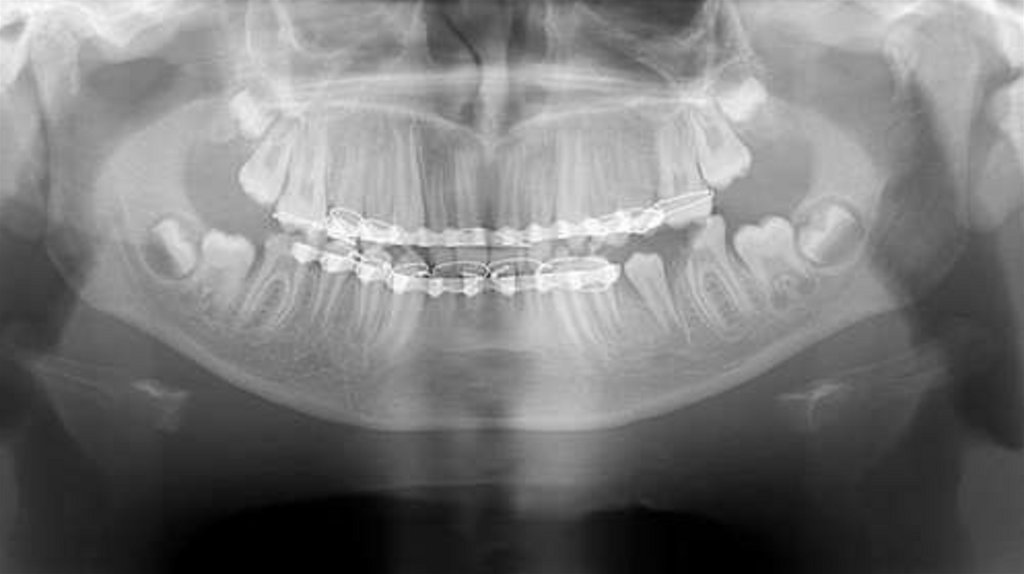

Были собраны подробные истории болезни, проведены

клинические и рентгенографические исследования, такие как

ортопантомография, окклюзионная рентгенография и

внутриротовая периапикальная рентгенография . После

тщательной оценки был поставлен диагноз типа перелома и был

составлен план лечения для каждого пациента.

Послеоперационные рентгенограммы были получены для

подтверждения заживления места перелома перед удалением

шины (рис. 5 и рис. 8), и все пациенты наблюдались в течение 12